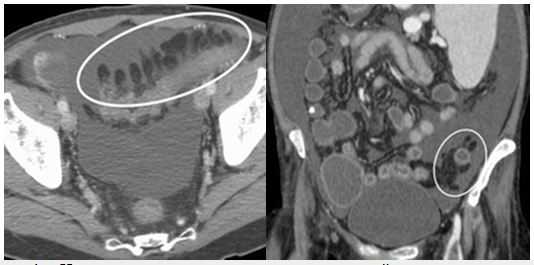

- овоидное образование жировой плотности прилежащее к толстой кишке, как правило 1.5-3.5 см в диаметре

- окруженное кольцевидной зоной повышенной плотности, толщиной 1-3 мм

- тяжистость окружающей клетчатки за счет воспаления, утолщение прилежащей брюшины

- центральное включение повышенной плотности (представленное тромбированной сосудистой ножкой)

- минимальное утолщение стенки прилежащей толстой кишки, не всегда присутствует, и гораздо менее выраженное чем воспалительные изменения жировой клетчатки

- аппендажит классически локализуется в передних отделах сигмовидной или нисходящей толстой кишки, но в целом может локализоваться в любом месте по ходу толстого кишечника

КТ особенности острого аппендагита — овальное образование 1,5-3,5 см в диаметре жировой плотности, окруженное воспалительными изменениями, которое прилежит к передней стенке сигмовидной ободочной кишки.

На рисунке 1. Нормальные жировые привески сигмовидной кишки очерчены асцитической жидкостью.

Наиболее распространенными местами аппендагита, в порядке убывания частоты, являются участки, прилегающие к сигмовидной кишке, нисходящей ободочной кишке, а также правого гемиколона. Наиболее распространенные КТ особенности острого аппендагита является овальный участок менее 5 см в диаметре (типичный диапазон диаметром 1,5-3,5 см), который имеет плотность жира, граничит с передней стенкой кишки и окружен воспалительными изменениями. Также может наблюдаться утолщение прилежащей париетальной брюшины. Стенка толстой кишки может быть утолщена, но наиболее часто нормальной толщины. Кишечная непроходимость и формирование абсцесса редки. В центре определяется участок повышенной плотности, однако его не исключает диагноз острого аппендагита. В редких случаях может возникнуть воспаление придатка в грыжевом мешке.

Динамическое сравнение КТ-картины при остром аппендагите в начале заболевания и через 3 месяца.